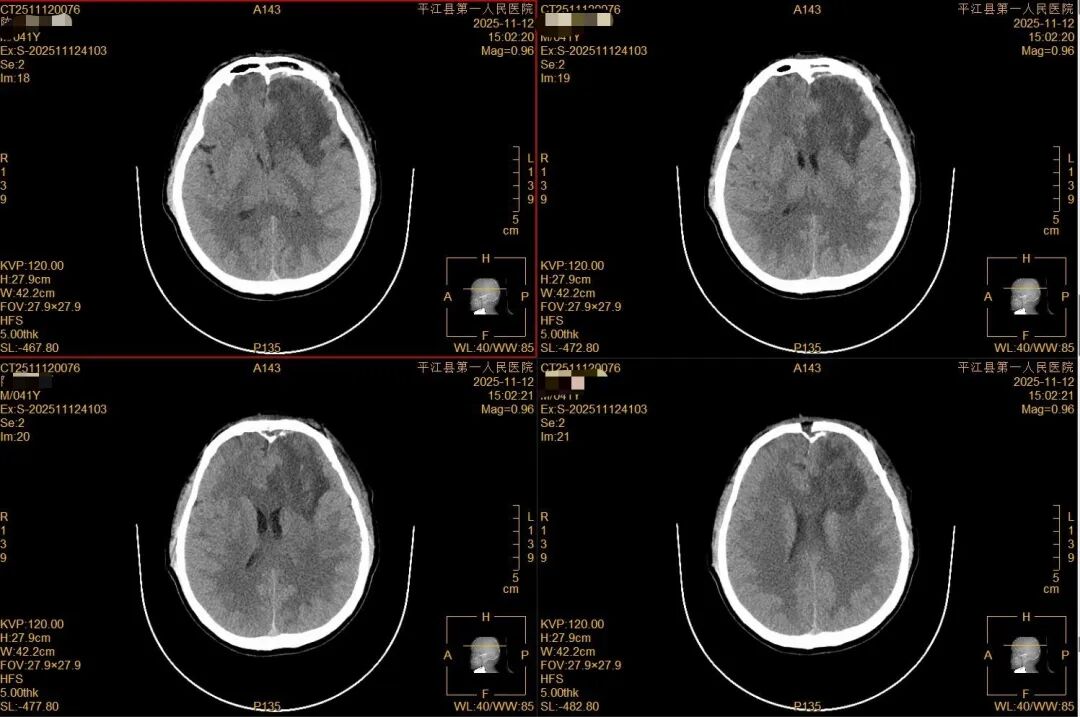

术后监护:患者术后直接转入ICU接受精细化监护,术后第5天各项指标稳定,顺利转入神经外科普通病房。

转入普通病房后,医护人员与家属通力协作、全程守护。陈先生恢复情况远超预期,如今已能自主行走、正常交流,生活基本自理,各项神经功能稳步向好,即将康复出院。

(▲图片说明:术后第9天颅脑CT显示)